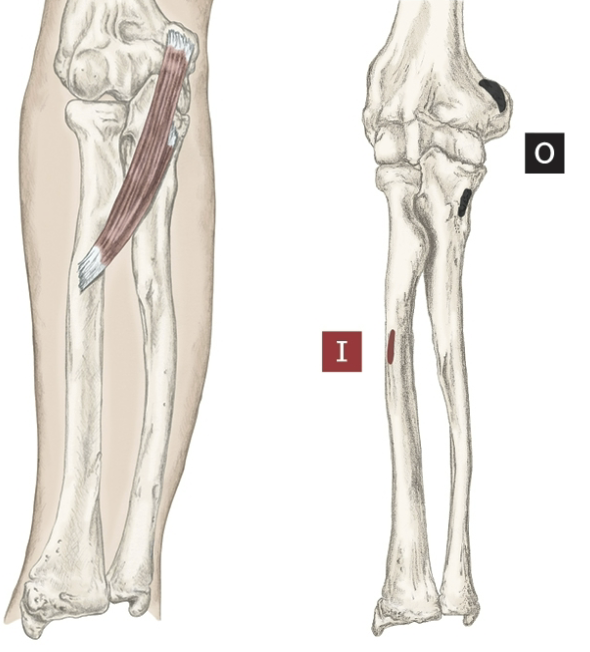

Action of Flexor Digitorum Profundus

Flexion of 2-5 fingers [ MCP,PIP,DIP]

Origin of Flexor Digitorum Profundus

Proximal ulna and anterior, and medial

Insertion of Flexor Digitorum Profundus

Base of palmar surface of distal phalanges 2-5

Nerve that the Flexor Digitorum Profundus innervates

Median Nerve